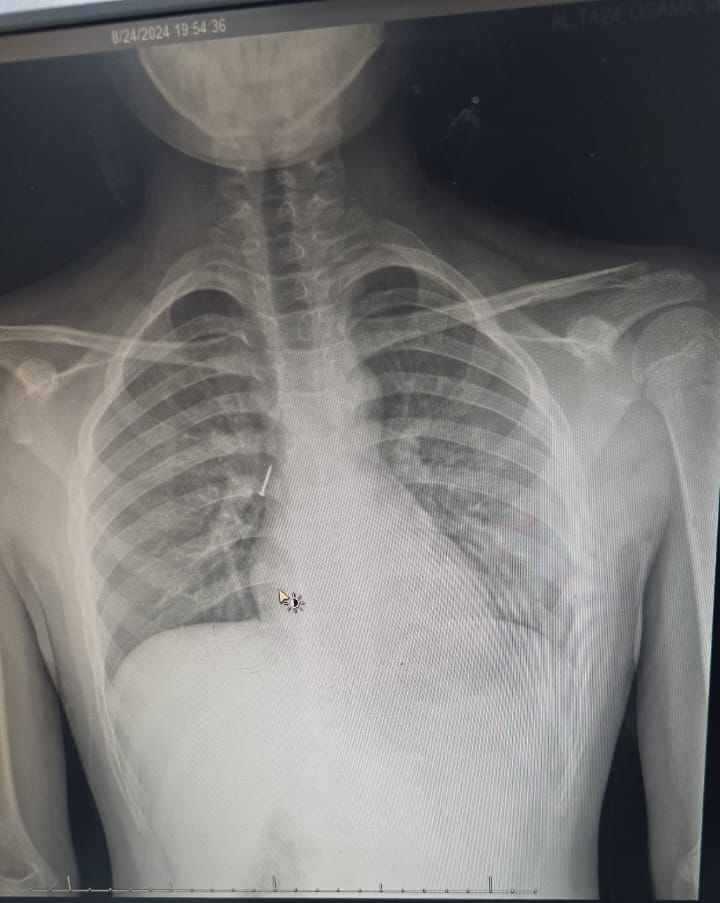

تمكن فريق طبي من قسم جراحة الأنف والأذن والحنجرة في مستشفى الملك خالد التابع لتجمع تبوك الصحي بمنطقة تبوك من انقاذ حياة طفل في العاشرة من عمره ابتلع مسماراً معدنياً مما تسبب له في ضيق في التنفس في الجهة اليمنى من الرئة وتضييق في الصدر.

وقال الفريق الطبي المعالج بأن الطفل وصل للطوارئ وكان يعاني من آلام شديدة في الحلق وضيق في التنفس وتم وضعه على الأكسجين بعد أن تم قياس العلامات الحيوية له , وبعد تقييم الحالة من قبل أخصائي الطوارئ وأخصائي الأطفال وأخصائي الأنف والأذن والحنجرة تقرر نقل الطفل إلى العناية المركزة للأطفال كما تم عمل أشعة مقطعية دقيقة على الشعب الهوائية حددت مكان المسمار المعدني بدقة.

وأكد الفريق الطبي المعالج بأنه تقرر على الفور إجراء عملية عاجلة لاستخراج المسمار المعدني بمنظار الشعب الهوائية تحت تخدير كامل للطفل من قبل فريق جراحة الأنف والأذن والحنجرة والتي تكللت ولله الحمد بالنجاح ولقد استغرق إجراء العملية ساعة كاملة, بعدها خرج الطفل من المستشفى وهو يتمتع بصحة جيدة ,مع المتابعة في عيادة الأنف والأذن والحنجرة.